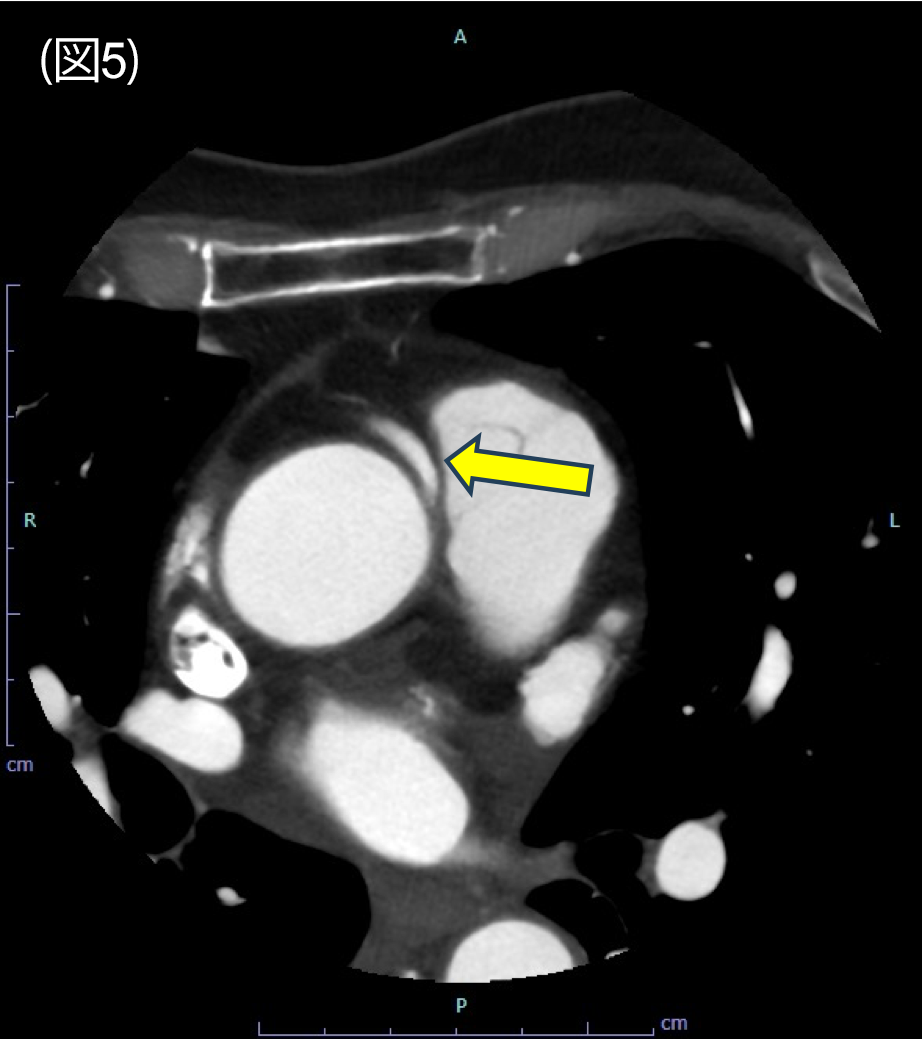

図5.冠動脈CT axial 像

右冠動脈は大動脈と肺動脈の間を走行している。